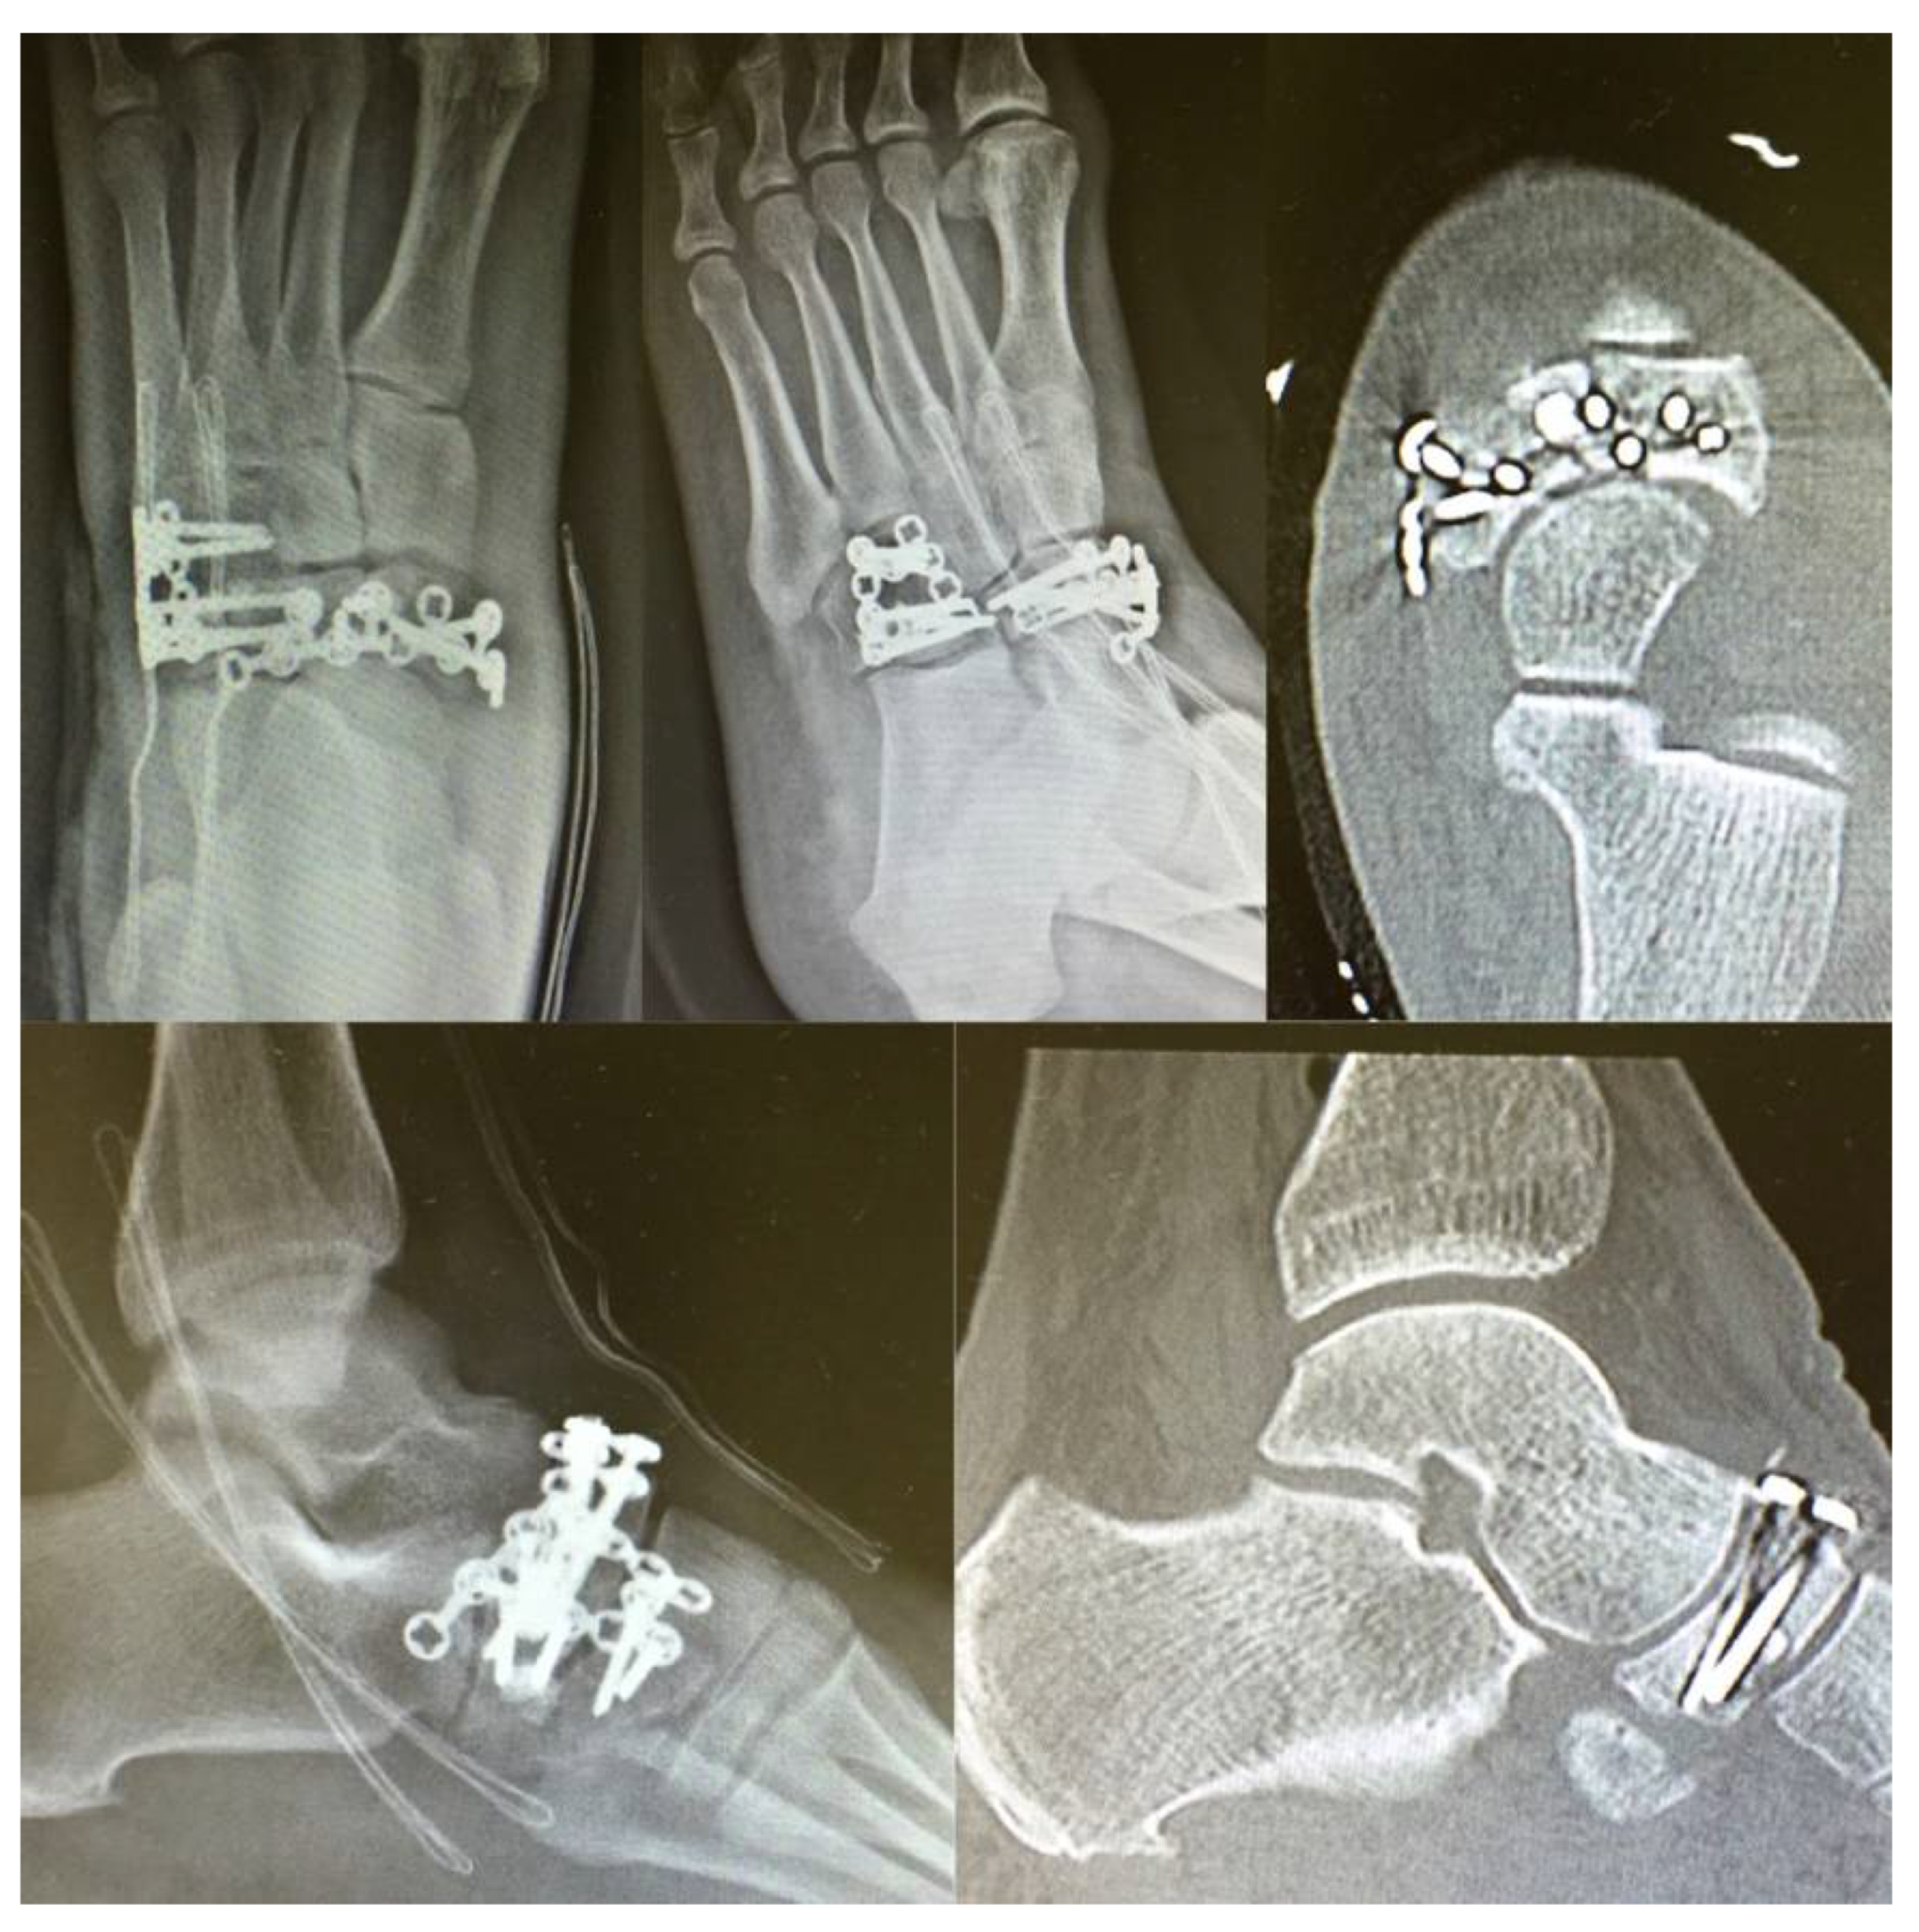

3. Surgical Procedure